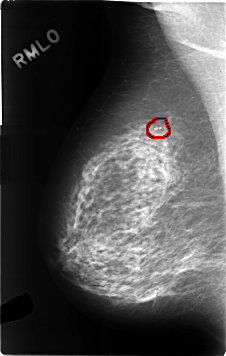

C_0310_1.RIGHT_MLO

FILE: C_0310_1.RIGHT_MLO.OVERLAY

TOTAL_ABNORMALITIES 1

ABNORMALITY 1

LESION_TYPE CALCIFICATION TYPE PLEOMORPHIC DISTRIBUTION CLUSTERED

ASSESSMENT 3

SUBTLETY 5

PATHOLOGY BENIGN

TOTAL_OUTLINES 1

BOUNDARY